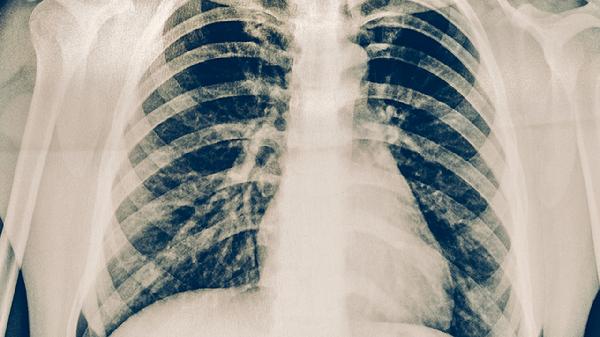

放射性肺炎患者除遵医嘱用药外,需保持居住环境空气流通,避免接触烟雾粉尘等刺激物。饮食宜选择高蛋白、高维生素的清淡食物,如鱼肉、鸡蛋、西蓝花等,有助于促进受损肺组织修复。适当进行呼吸功能锻炼,如腹式呼吸、缩唇呼吸等,但应避免剧烈运动。定期复查胸部影像学,监测病情变化。若出现发热、呼吸困难加重等情况需立即就医。